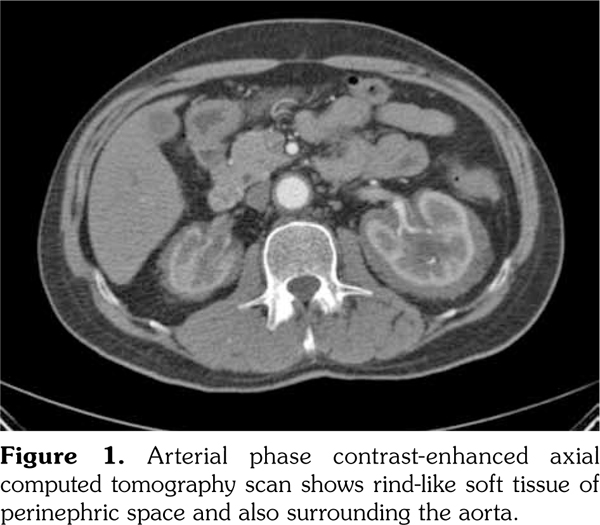

A 51-year-old male patient admitted to our outpatient clinic with complaints of flank pain and fatigue. He had a history of renal stones and peripheral arterial disease. He had a medically unmanageable hypertension. Blood pressure was 200/110 mmHg. Serum creatinine level was 1.2 mg/dL. He was evaluated with contrast- enhanced multislice computed tomography. Along with small calyceal stones, there was bilateral, quite symmetrical perinephric ''rind-like'' soft tissue infiltration. Right kidney was atrophic but still functioning without pelvicalyceal contrast excretion. The soft tissue infiltration obliterated both renal hila and caused proximal ureteral stenoses with mild calyceal dilation on the left side (Figures 1 and 2). Distally, the ureters were normal. Incidentally, abdominal aorta, common iliac arteries, proximal celiac trunk, and proximal renal arteries were noticed to appear “coated” with subtle perivascular tissue infiltration. An endovascular aortoiliac stent-graft was in place. He rejected any further diagnostic intervention after he presented with a blood creatinine of 2.2 mg/dL. He underwent an unenhanced computed tomography examination with the same findings before. Renal scintigraphy revealed a non-functioning right kidney. Perinephric soft tissue infiltration was considered as the differential diagnosis of ECD. Direct radiographies of the extremities were obtained. All of the long tubular bones showed diametaphyseal cortical and patchy medullary sclerosis reinforcing the diagnosis of ECD (Figure 3). The patient underwent right nephrectomy for the control of hypertension and a double-J stent was placed on the left side for the relief of ureteral obstruction. The nephrectomy specimen showed the typical histological features of ECD. Serum creatinine level dropped to the borderline values after the operation and his blood pressure was in the normal range with medications. The pathological analysis of the nephrectomy specimen revealed an inflammatory infiltrate formed by foamy histiocytes that were positively stained for CD68 and neutrophilic aggregates which confirmed the preoperative diagnosis (Figures 4 and 5). A written informed consent was obtained from the patient.

The X-ray changes that are considered to be pathognomonic and found in almost all patients are dia-metaphyseal osteosclerosis bilaterally and symmetrically in the tubular bones of upper and lower extremities.(5) They also show an increased uptake of tracer on Technetium 99m bone scintigraphy.(4) These bone changes may be misdiagnosed as Paget’s disease, lymphoma, sarcoidosis, metastases, or lipid storage diseases.(6,7)

In our case, computed tomography findings suggested retroperitoneal fibrosis but the infiltrate did not involve the vena cava and the paraaortic infiltration was circumferential instead of sparing the posterior aspect of the aorta. Also, the perinephric infiltration was far more striking than the perivascular space which is inconsistent with retroperitoneal fibrosis. Therefore, the differential diagnosis consisted mainly of processes involving perinephric and perivascular spaces, namely, lymphoma, retroperitoneal fibrosis, and ECD. The diagnosis of ECD was strongly suggested with the radiographic findings of the extremities which revealed symmetrical dia-metaphyseal osteosclerosis.